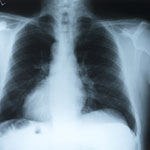

יום המודעות העולמי למחלת COPD

אחד מכל חמישה מעשנים יחלה ב- COPD, הגורם המוביל למוו...